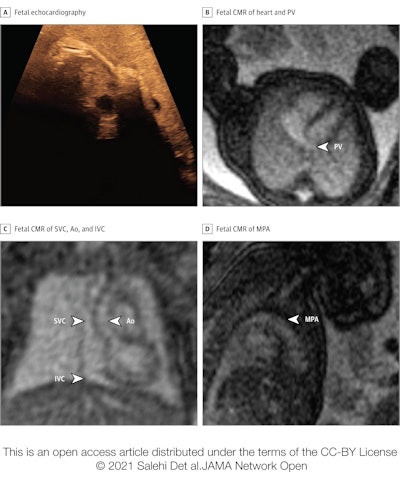

Congenital heart defects are typically identified in utero by echocardiography, but sometimes that modality proves inconclusive due to inadequate acoustic windows. In recent years researchers have developed an MR-compatible Doppler ultrasound device that allows for the acquisition of high-resolution fetal cardiovascular MR (CMR) images without postprocessing.

Salehi and colleagues sought to investigate the efficacy of fetal CMR after inconclusive echocardiography, as well as whether its use resulted in any patient management or parental counseling changes. The team conducted a study of 31 fetuses referred for cardiovascular MRI at Skåne University Hospital in Lund between January 2017 and June 2020; fetuses had a median gestational age of 36 weeks.

The authors found that cardiovascular MRI affected patient management and/or parental counseling in 84% of the cases, and added useful diagnostic and/or management information to the following situations: